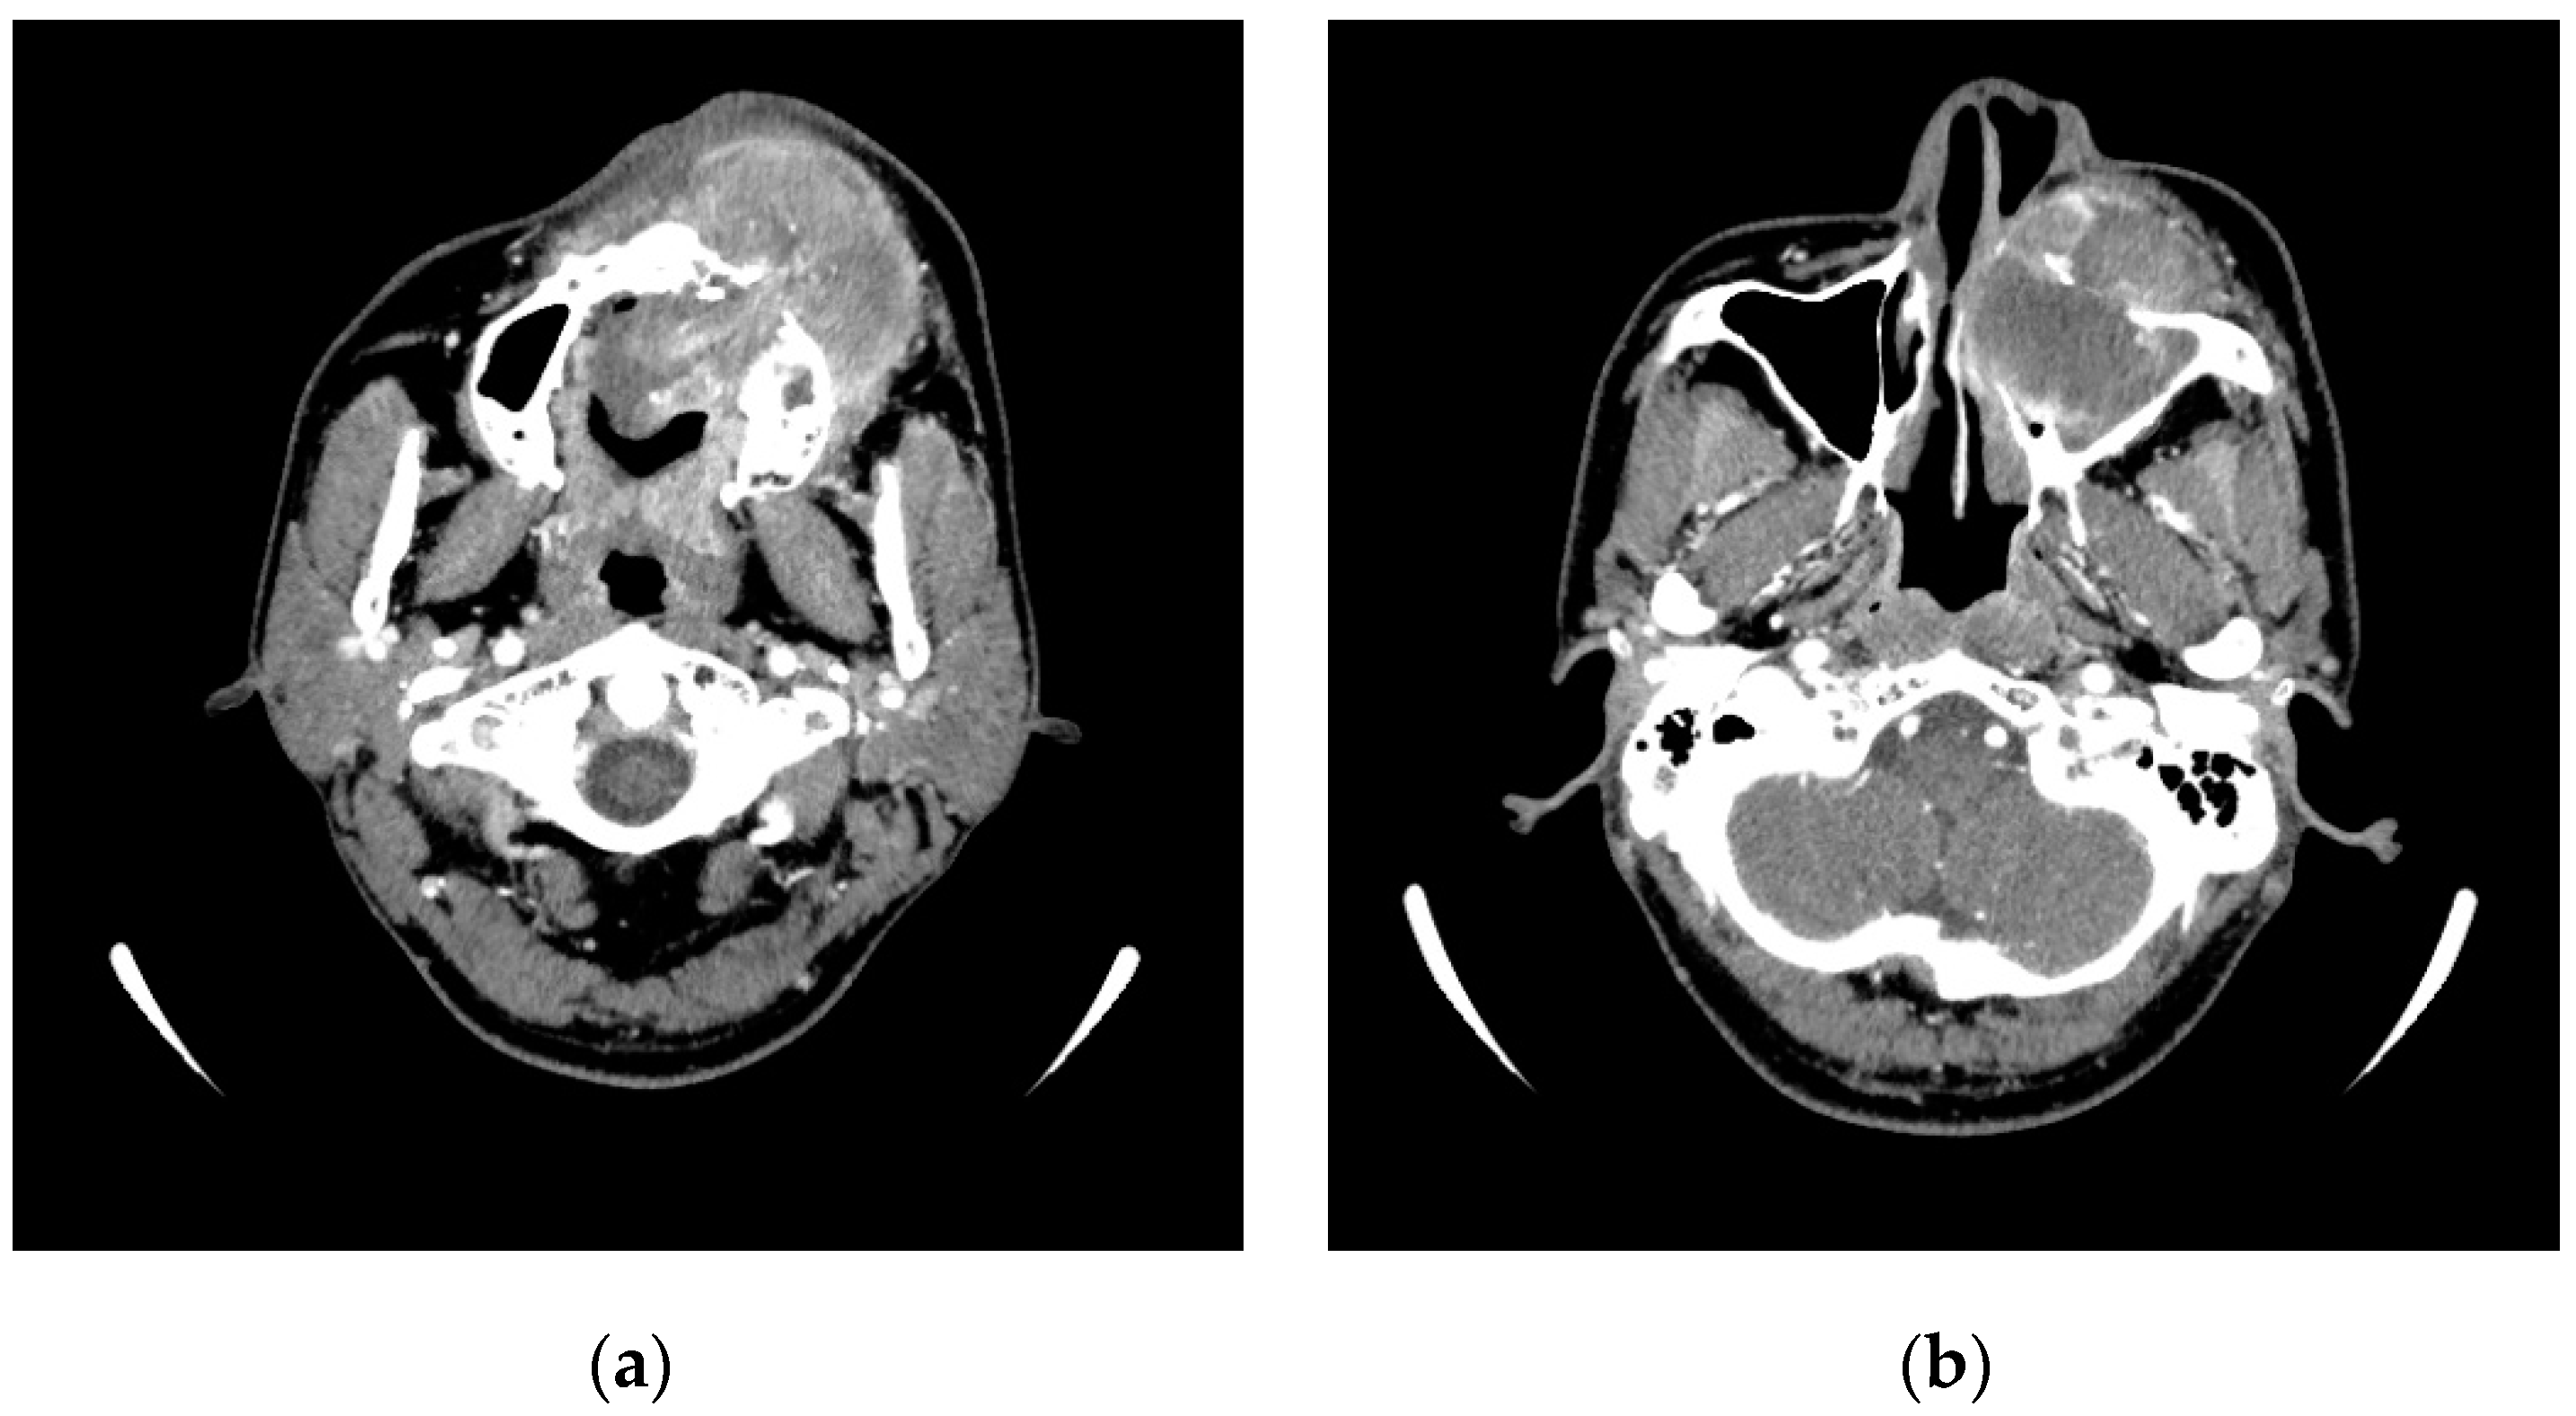

2. Case Presentation